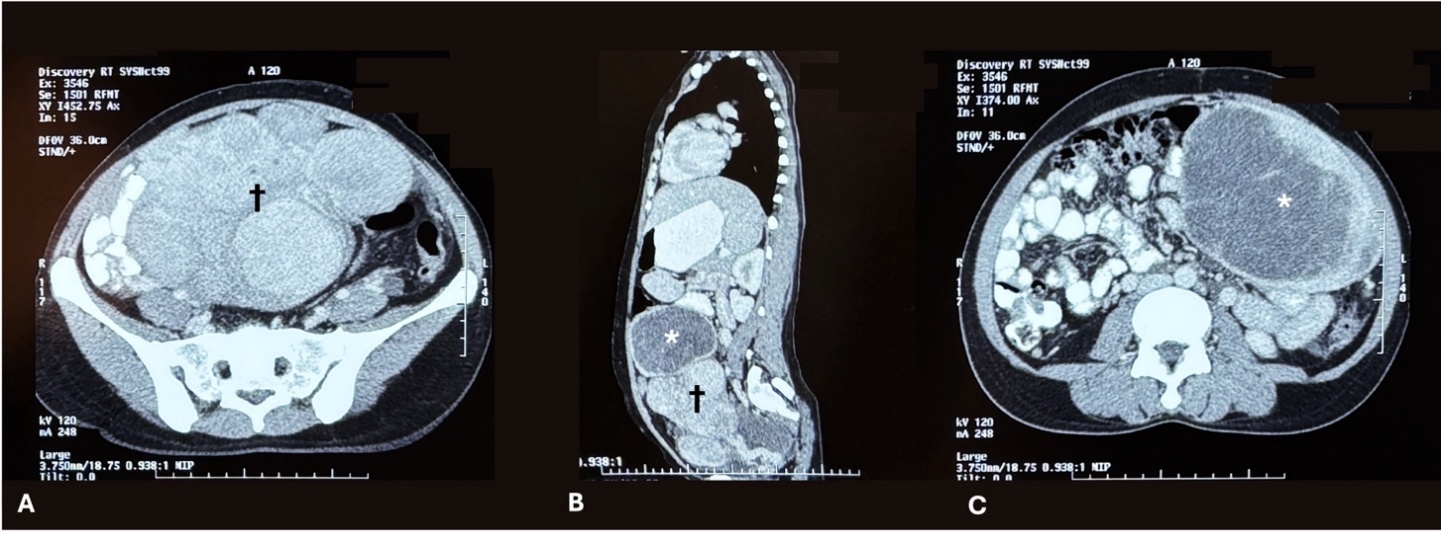

Ultrasonography revealed a very large heterogeneously hypoechoic whorled appearing round to oval lesion in the pelvic cavity extending into the umbilical region & right iliac fossa measuring approximately 156 X 169 X 213 mm with increased intralesional vascularity suggestive of uterine leiomyoma. Further on contrast-enhanced computed tomography, a large well-demarcated, heterogeneous, irregular, predominantly peripherally enhancing mass lesion centred in the small bowel mesentery with a necrotic core and lobulated outer margins with intact fat planes was detected, likely to be GIST (Figure 1).

On contrast-enhanced CT, both GIST and parasitic leiomyoma may appear as well-defined, heterogeneously enhancing masses with necrotic or cystic areas [3,7]. GISTs typically arise from the bowel wall and often demonstrate an exophytic growth pattern, whereas parasitic leiomyomas may display a whorled architecture similar to uterine fibroids and coexist with uterine myomas [7]. In our patient, the absence of a clear bowel wall origin suggested a non-gastrointestinal source; however, imaging alone was insufficient to exclude GIST. Definitive diagnosis required histopathology and immunohistochemistry demonstrating strong SMA positivity with negativity for CD117 and DOG1.